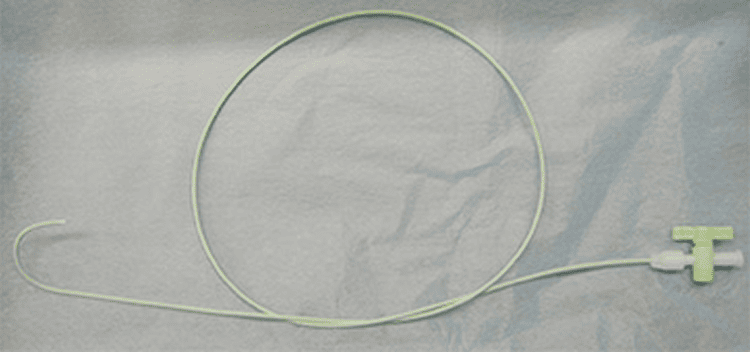

エックス線透視像やCT画像を見ながら体内に細い管(カテーテルや針)を入れてを操作し、悪性腫瘍、血管性病変、出血などに対して治療を行うものです。

動脈内に入れて癌の栄養動脈まで達するための管。

この管を利用して栄養動脈を塞栓する

カテーテルの中に入れてカテーテルを誘導するもの